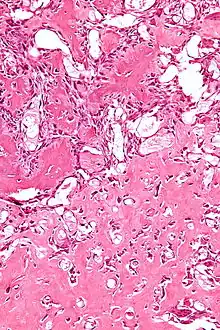

The cause of osteoblastoma is unknown. Histologically, osteoblastomas are similar to osteoid osteomas, producing both osteoid and primitive woven bone amidst fibrovascular connective tissue, the difference being that osteoblastoma can grow larger than 2.0 cm in diameter while osteoid osteomas cannot. Although the tumor is usually considered benign, a controversial aggressive variant has been described in the literature, with histologic features similar to those of malignant tumors such as an osteosarcoma.

Biopsy

A biopsy is usually required to confirm diagnosis.[1]